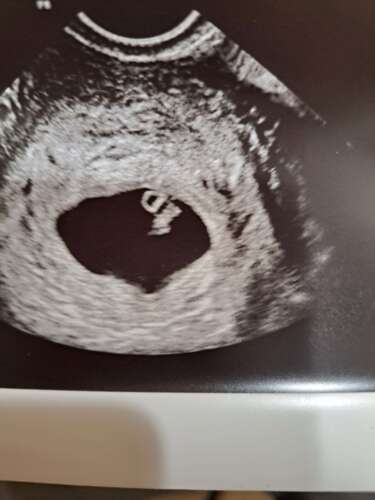

Gisteren 31-10-23 , 6+6 weken. Ons wondertje 🥰